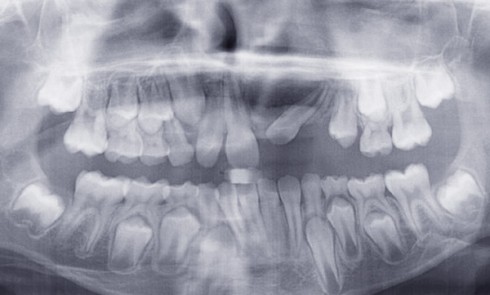

Examen clinique Le jeune Yoan 9 ans est adressé par son chirurgien maxillofacial, suite à l’exérèse d’un kyste bénin du...